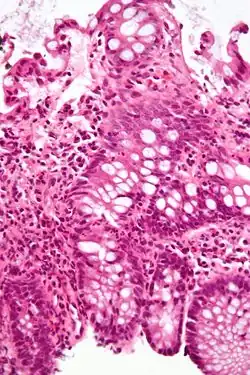

| A micrograph demonstrating cryptitis, a microscopic correlate of colitis. H&E stain. | |

An important investigation in the assessment of colitis is biopsy for histopathology. A very small piece of tissue (usually about 2mm) is removed from the bowel mucosa during endoscopy and examined under the microscope by a histopathologist. A biopsy report generally does not state the diagnosis, but should state any presence of chronic colitis, give an indication of disease activity, as well as state the presence of any epithelial damage (erosions and ulcerations).[6]

Histopathology findings generally associated with chronic colitis include:[6]

Crypt degeneration -

Crypt branching and other architectural distortions -

Paneth cell (pictured) or gastric metaplasia (only applies in the left colon and rectum)

Other findings include basal plasmacytosis and mucin depletion.[6] Histopathology findings generally associated with active colitis include:[6]

-

Neutrophilic cryptitis (neutrophils within crypt epithelium) -

Crypt abscesses (luminal neutrophilic aggregates) -

Gland destruction -

Ulceration (seen here as absence of epithelium, and granulation tissue with many fibroblasts)